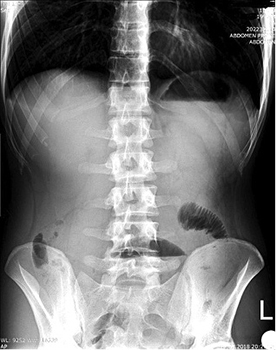

The plain radiograph showed signs of small bowel obstruction (Figure 1).

20.jpg Figure 1